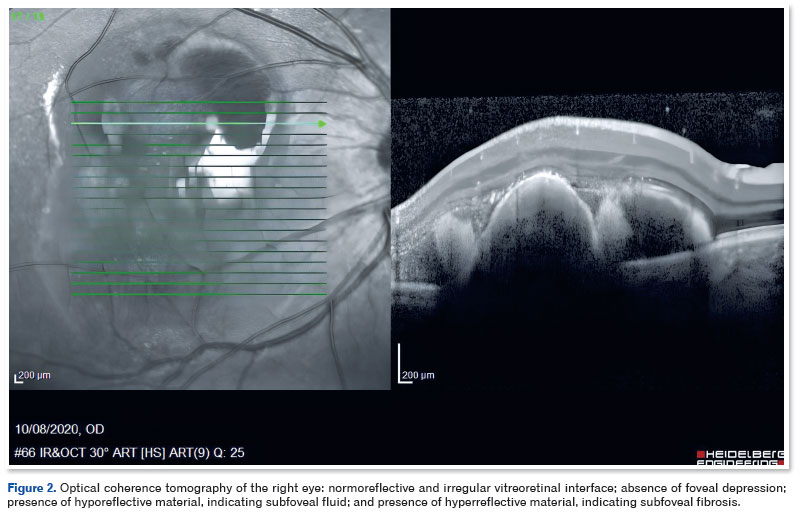

A 39-year-old man diagnosed with DM1 in early childhood (through a PCR test with capillary electrophoresis and Southern blot that detected pathological repeats of the CTG trinucleotide in DMPK) reported recent vision loss in the OD. On ophthalmologic examination, corrected visual acuity (CVA) was 20/100 in the OD and 20/20 in the OE. Biomicroscopy showed clear conjunctiva, transparent cornea, no reaction in the anterior chamber, and clear lens in both eyes. Extrinsic eye movement was preserved in both eyes. Retinal imaging showed subretinal hemorrhage in the macular area, associated with exudation in the OD (Figure 1). No retinal changes were observed in the OS. The findings of fluorescein angiography were hypofluorescence due to blockage in the macular area of the OD. Optical coherence tomography (OCT) revealed a normoreflective and irregular vitreoretinal interface, absence of foveal depression, presence of hyporeflective material indicating subfoveal fluid, and presence of hyperreflective material, suggesting subfoveal fibrosis (Figure 2).